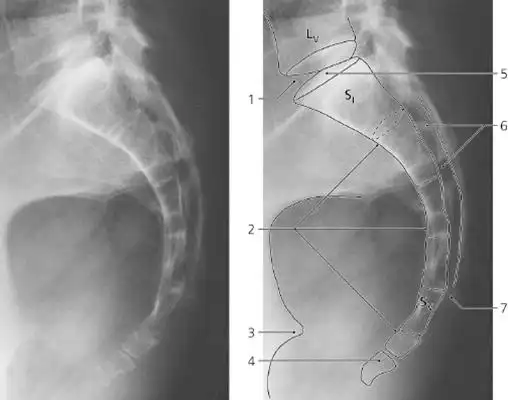

骶尾椎影像报告怎么写? - 知乎